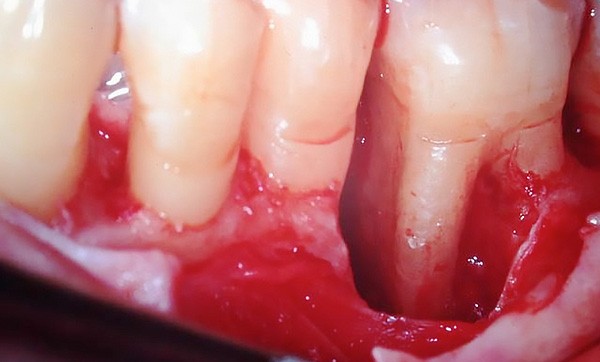

La présence de défauts infraosseux est caractéristique de la maladie parodontale, maladie inflammatoire d’origine infectieuse. Le but du traitement parodontal, après le contrôle de l’inflammation, est la reconstruction des tissus parodontaux détruits, se traduisant cliniquement par une diminution de la profondeur des poches et un gain d’attache clinique. Si, en raison des limites biologiques de la cicatrisation, la reconstruction des tissus parodontaux détruits est impossible lorsque la résorption osseuse est horizontale, il est possible de l’obtenir en présence de défauts infraosseux.

Au fil du temps, différentes techniques chirurgi­cales ont été proposées pour reconstruire les tissus parodontaux en présence de défauts infra­osseux, depuis les premières greffes osseuses jusqu’à l’utilisation plus récente des facteurs de croissance [9].

Seule l’étude histologique permet de prouver que la régénération a été obtenue, caractérisée par la néoformation d’os, de cément et de ligament parodontal [18, 28].

De nombreux facteurs liés au patient, à la morphologie du défaut et à la technique chirurgicale influencent l’efficacité et la prévisibilité des résultats. Ils méritent d’être passés en revue avant d’étudier chacune des techniques de régénération.

Facteurs liés à la morphologie du défaut

Les défauts osseux doivent être évalués selon leur profondeur, leur largeur et leur nombre de parois.

Le défaut doit pouvoir contenir le caillot sanguin et assurer un maintien de l’espace nécessaire à la régénération.

Un défaut dont la profondeur dépasse 3 mm est plus favorable à l’application d’une technique de régénération [10] tandis qu’un défaut à une paroi est un facteur de risque d’échec [5].